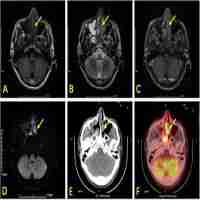

| Abstract | Purpose: We investigated the utility of a new baseline PET parameter expressing lesion dissemination and metabolic parameters for predicting progression-free survival (PFS) and pathologic grade in follicular lymphoma (FL). Methods: Baseline 18F-FDG PET/CT images of 126 patients with grade 1-3A FL were retrospectively analysed. A novel PET/CT parameter characterizing lesion dissemination, the distance between two lesions that were furthest apart (Dmax), was calculated. The total metabolic tumor volume and total lesion glycolysis (TLG) were computed by using the 41% maximum standardized uptake value (SUVmax) thresholding method. Results: The 5-year PFS rate was 51.9% for all patients. In the multivariate analysis, high Dmax [P=0.046; hazard ratio (HR)=2.877], high TLG (P=0.004; HR=3.612), and elevated serum lactate dehydrogenase (P=0.041; HR=2.287) were independent predictors of PFS. A scoring system for prognostic stratification was established based on these three adverse factors, and patients were classified into three risk categories: low-risk (0-1 factor, n=75), intermediate-risk (2 adverse factors, n=29), and high-risk (3 adverse factors, n=22). Patients in the high-risk group had shorter 3-year PFS (21.7%) than those in the low- and intermediate-risk groups (90.6% and 44.6%, respectively) (P<0.001). The C-index of our scoring system for PFS (0.785) was superior to the predictive capability of the Follicular Lymphoma International Prognostic Index (FLIPI), FLIPI2, and PRIMA-Prognostic Index (C-index: 0.628-0.701). The receiver operating characteristic curves and decision curve analysis demonstrated that the scoring system had better differentiation and clinical utility than these existing indices. In addition, the median SUVmax was significantly higher in the grade 3A (36 cases) than in grade 1-2 FL (90 cases) [median: 13.63 vs. 11.45, P = 0.013], but substantial overlap existed (range: 2.25-39.62 vs.3.17-39.80 ). Conclusion: TLG and Dmax represent two complementary aspects of the disease, capturing the tumor burden and lesion dissemination. TLG and Dmax are promising metrics for identifying patients at high-risk of progression or relapse. Additionally, SUVmax seems to have some value for distinguishing grade 3A from low-grade FL but cannot substitute for biopsy. |